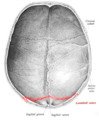

The lambdoid suture (or lambdoidal suture) is a dense, fibrous connective tissue joint on the posterior aspect of the skull that connects the parietal bones with the occipital bone. It is continuous with the occipitomastoid suture.

Its name comes from its uppercase lambda-like shape.

The lambdoidal suture articulates with the occipital bone and parietal bones.